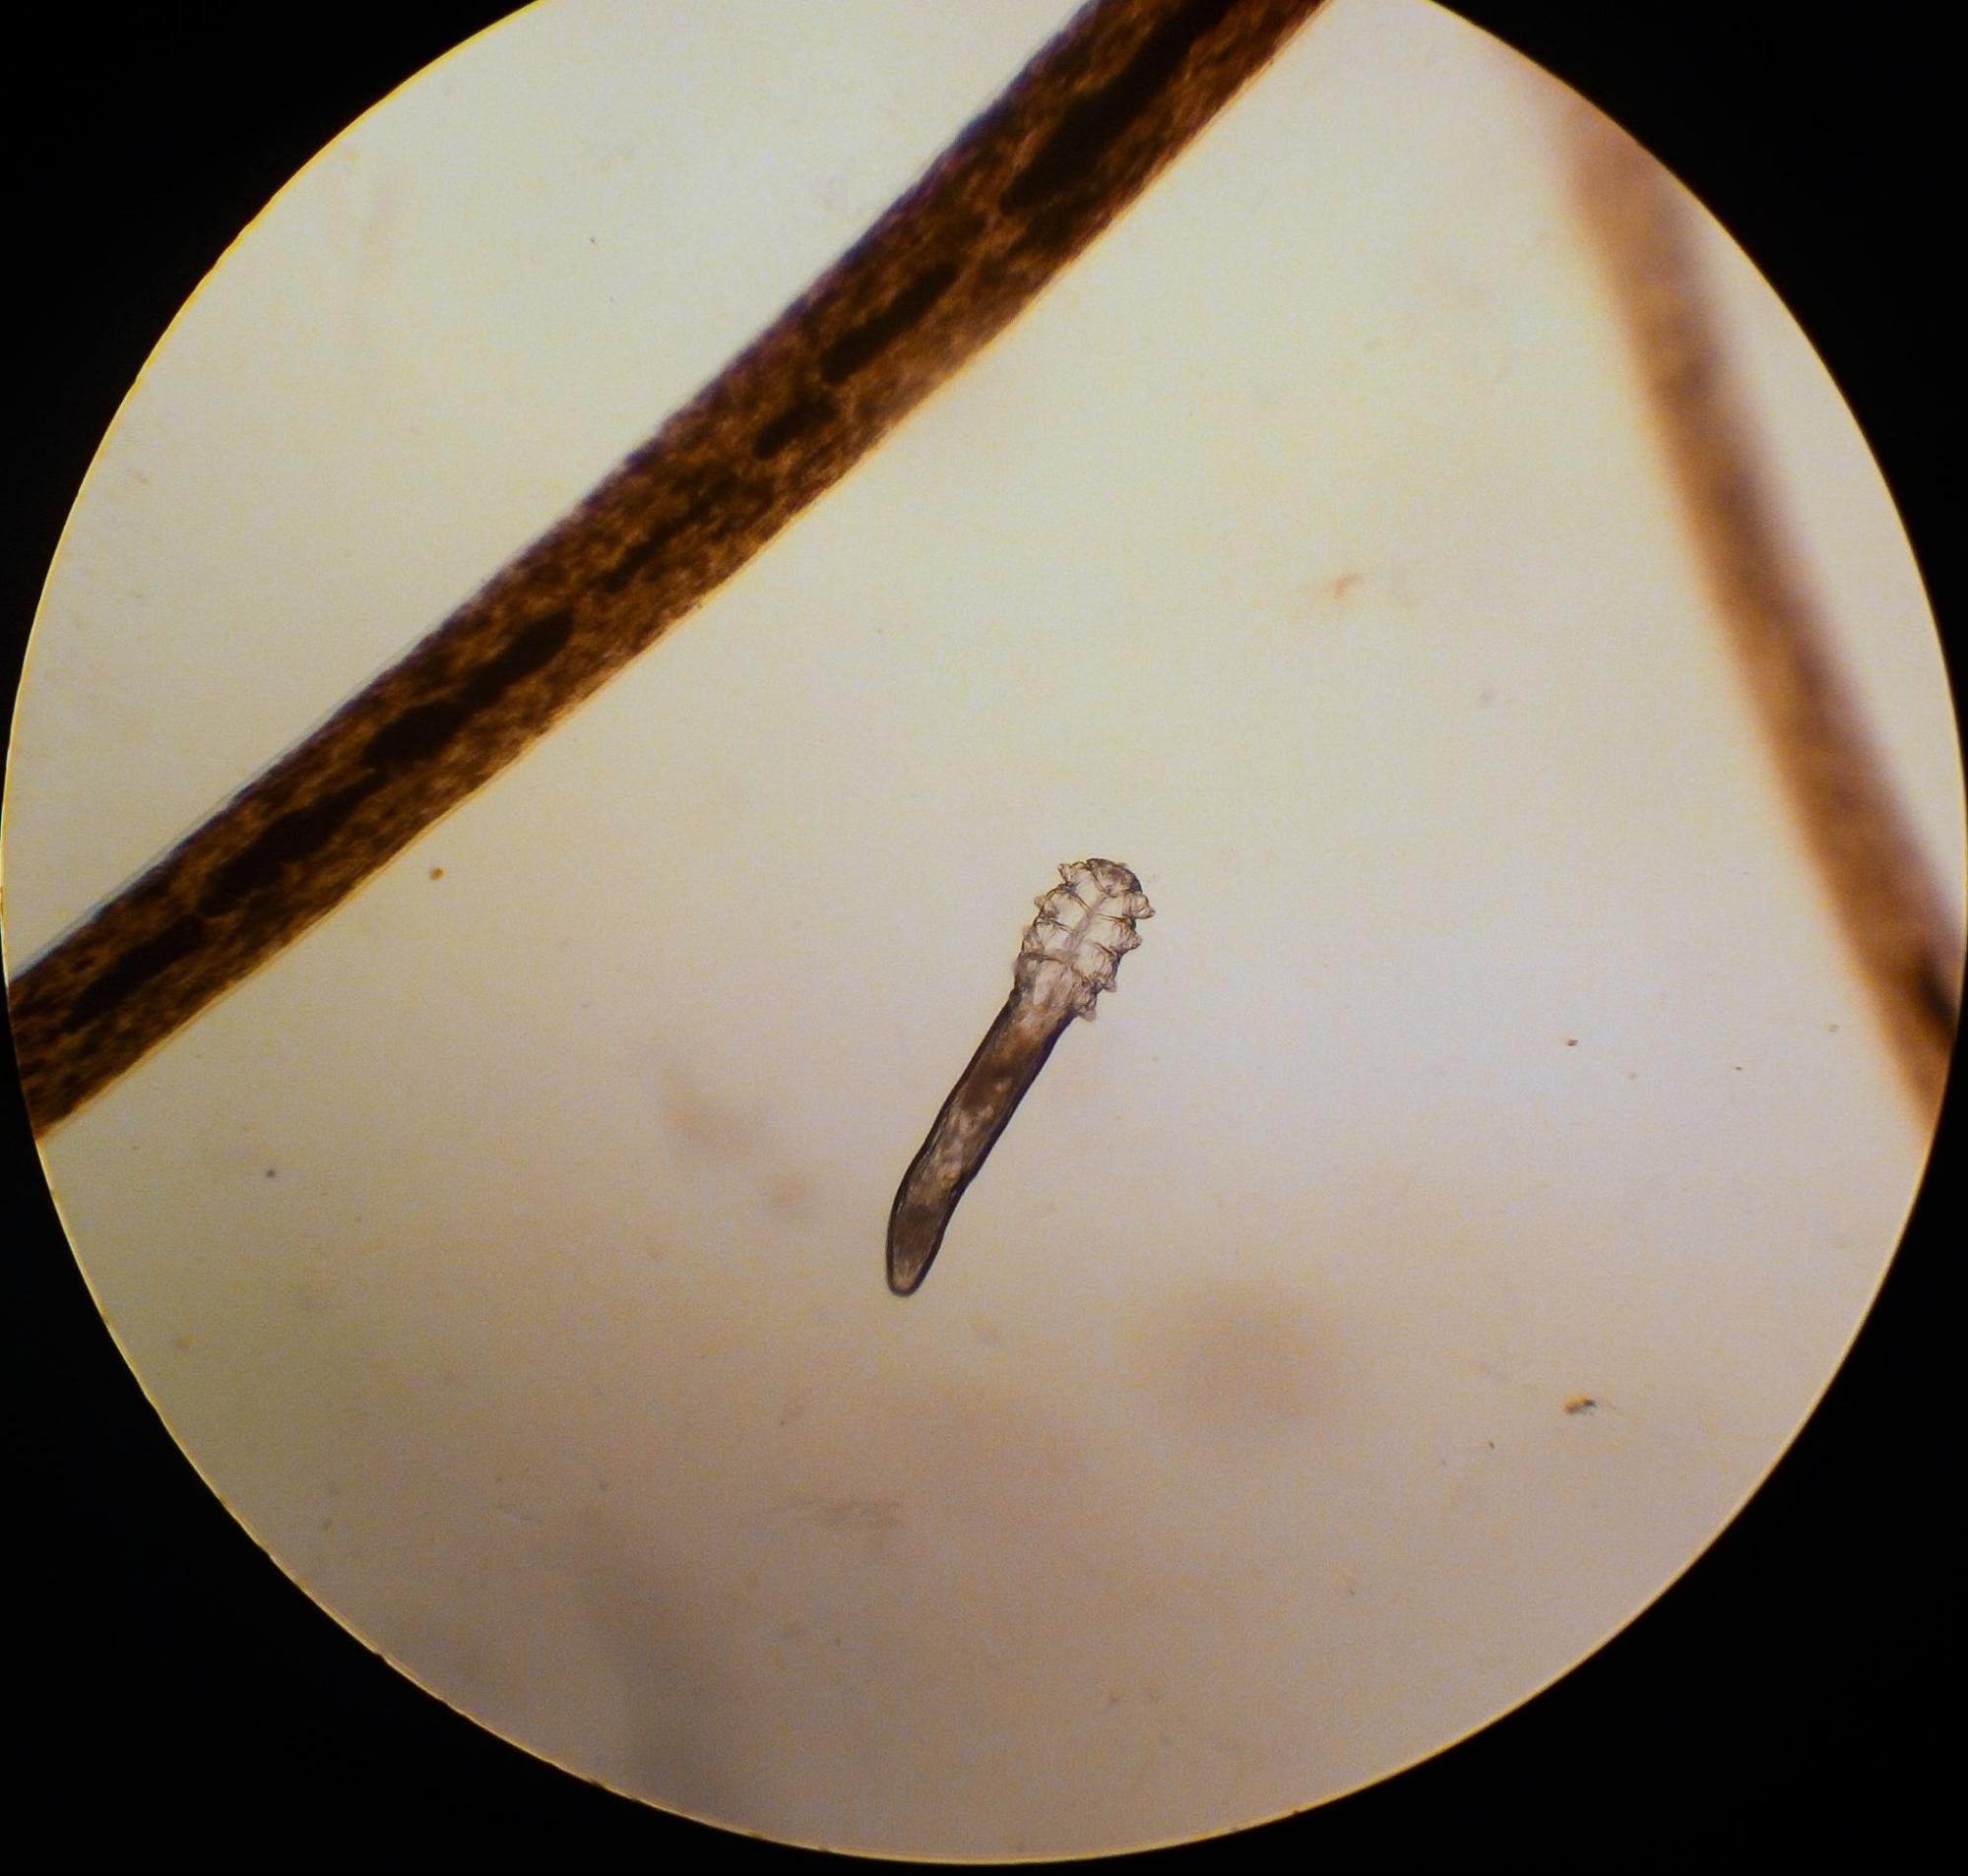

Demodex mite next to an eyelash under a microscope

Demodexfolliculorum are typically 0.30mm to 0.40mm in length and found in clusters around the lash root and lash follicle. They feed on sebum and follicular epithelial cells.

Demodexbrevis is slightly smaller at 0.15mm to 0.20mm in length and travels alone, preferring to infest the meibomian glands (the glands that produce a secretion to keep the tears from evaporating too quickly).